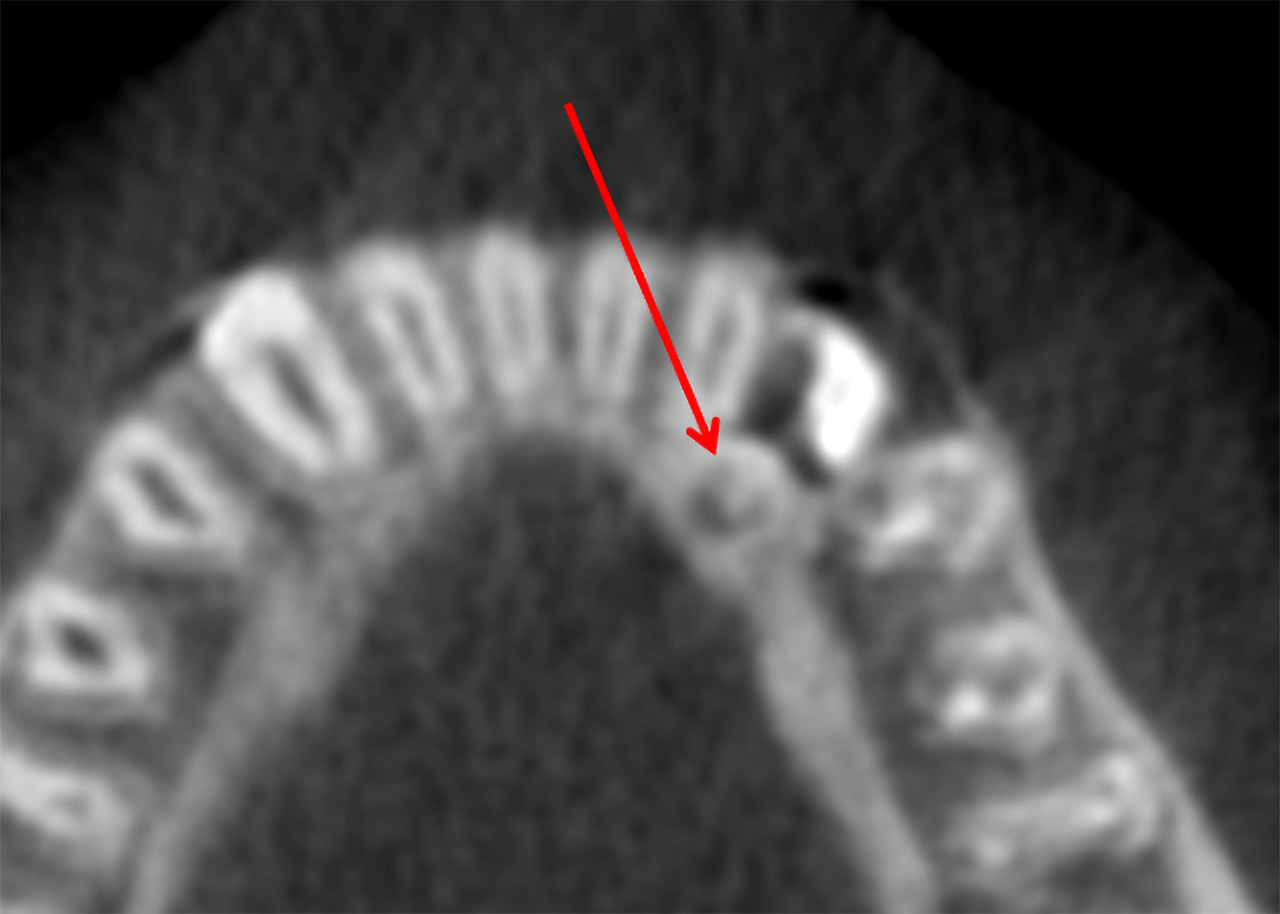

One lower wisdom tooth had tipped forward at nearly a 45-degree angle, wedging itself beneath the adjacent second molar. From another angle, the tooth appeared even more severely angled, closer to 60-80 degrees.

Eventually, the decay extended to the root surface of the second molar, as shown in the X-ray below.